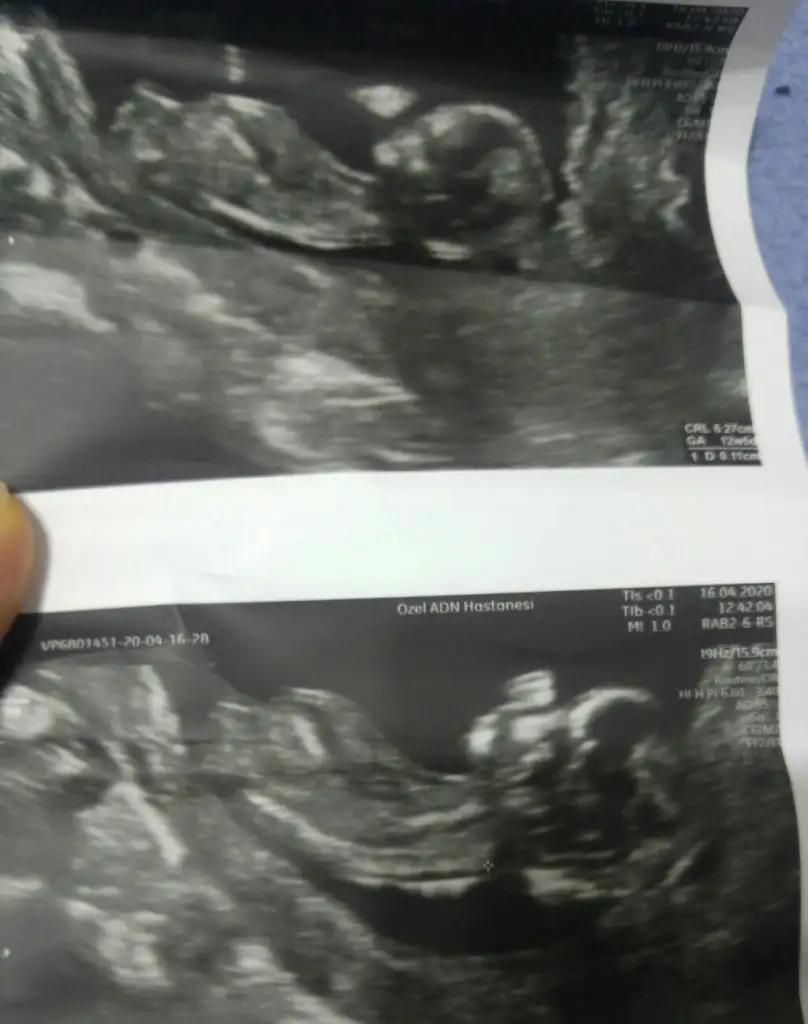

akadaşlar merhaba, ultrason görüntülerini paylaşsam bakabilir misiz.? meraktan çatlıyor insan 😍

Ultrason görüntülerimiz😍

yaa 😍 bende kız diye gördüm ama emin olamadım. bu nub teorisi inşallah doğrudur 😂 allah gönlümüze göre versin 😊 senin bebişin cinsiyeti kesinleşti mi peki

Yok canım 14 de gittim giremedi kemik.yapısı kız dedi ama kordon un arkasında bir şey de var sanki dedi ogrenemdim inşaallah bu teori doğrudur da kız olur 😂😂